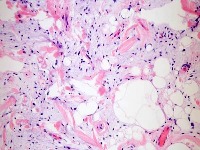

Fibrosarcoma

Liposarcoma

Undifferentiated Pleiomorphic Sarcoma